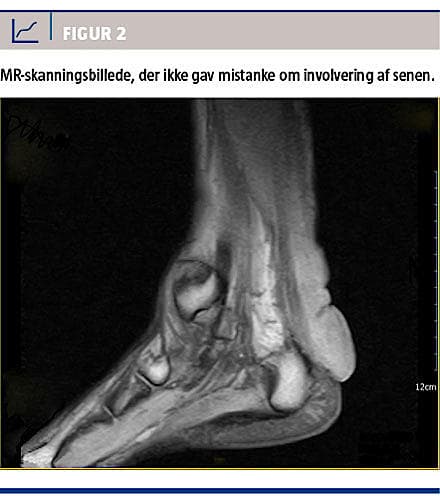

En 24-årig mand blev henvist til Dronning Ingrids Hospital i Nuuk med voksende, patologisk verificerede xantomer over begge akillessener og albuer. Hans body mass index var 33 kg/m2, han havde arcus cornea og forhøjet plasmalipidniveau, men havde ikke forhøjet blodtryk (Tabel 1). Plasmalipidniveauet havde været forhøjet, siden det først blev målt i 2010. Man havde forsøgt med kolesterolsænkende behandling, men kompliansen var utilstrækkelig, og behandlingen blev indstillet. Information om familiære dispositioner var sparsom. Patienten kunne dog oplyse, at hans far og faster havde haft xantomer af lignende karakter og placering. Fasteren var blevet opereret for dette med god effekt. Faderen døde som 42-årig, hvilket ifølge patienten skyldtes »noget med hjertet«. Der var ikke blevet konstateret familiær hyperkolesterolæmi. Patienten havde haft xantomerne siden barndommen, og de voksede fortsat. Af journalen fremgik det, at han første gang i 2004 var vurderet for »knudedannelser omkring akillessenerne«. Dengang havde man tolket det som mulige calcaneuseksostoser og vurderet, at det ikke var hæmmende for gangfunktionen. Da patienten blev tilset hos os i juli 2014, var de hårde forandringer til stede over akillessenerne og albuerne. Ved hælene var xantomerne så store, at patienten ikke kunne benytte almindeligt fodtøj (Figur 1). En MR-skanning viste, at der ikke var infiltration i senerne (Figur 2), og vi valgte derfor en kirurgisk tilgang, hvor man via en incision i huden på medialsiden af akillessenerne kom ind til adskillige mere eller mindre afgrænsede, hårde kolesterolklumper som infiltrerede hud, underhud og toppen af subcutis. De største tumorer var placeret lige over senernes tilhæftning på calcaneus og var her ca. 4 × 4 × 3 cm. Vi underminerede delvist, og det lykkedes at få store mængder ud, men det var umuligt at fjerne det hele. Lidt af huden blev reseceret, og der blev foretaget primær suturering med efterfølgende bandagering og anlæggelse af bagre gips i 14 dage. Resultatet blev kosmetisk forbedring samt mulighed for at bære fodtøj igen, dog med besvær.